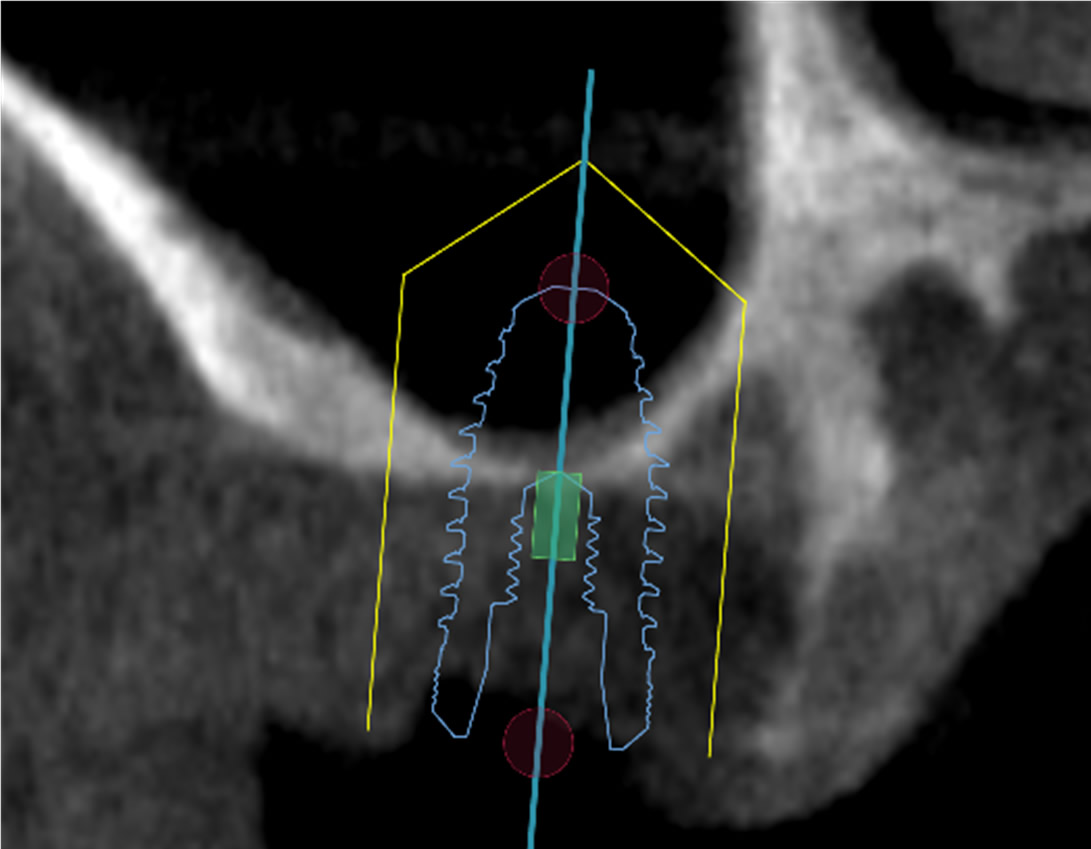

⑤ガイデッド手術によりインプラント埋入します

⑤ガイデッド手術で正確にインプラント埋入します